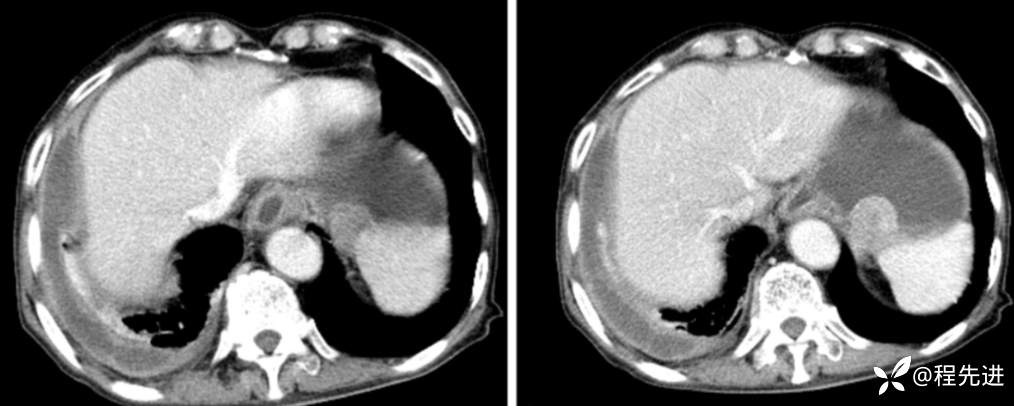

延迟期

局部放大